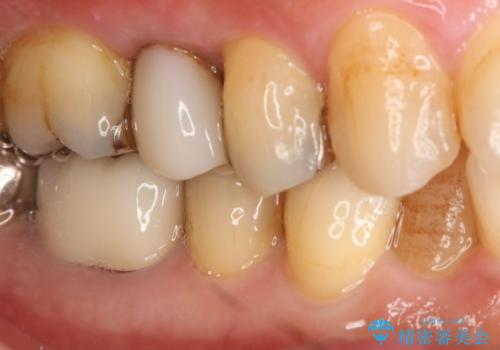

- 保険で治療された右下5番をセラミックにやり変え希望の患者様です。

切削量などを考慮し、セラミックインレーでの治療を選択しました。

古い材料と虫歯を全て除去した上で形成・印象を行い、セラミックインレーを装着しています。